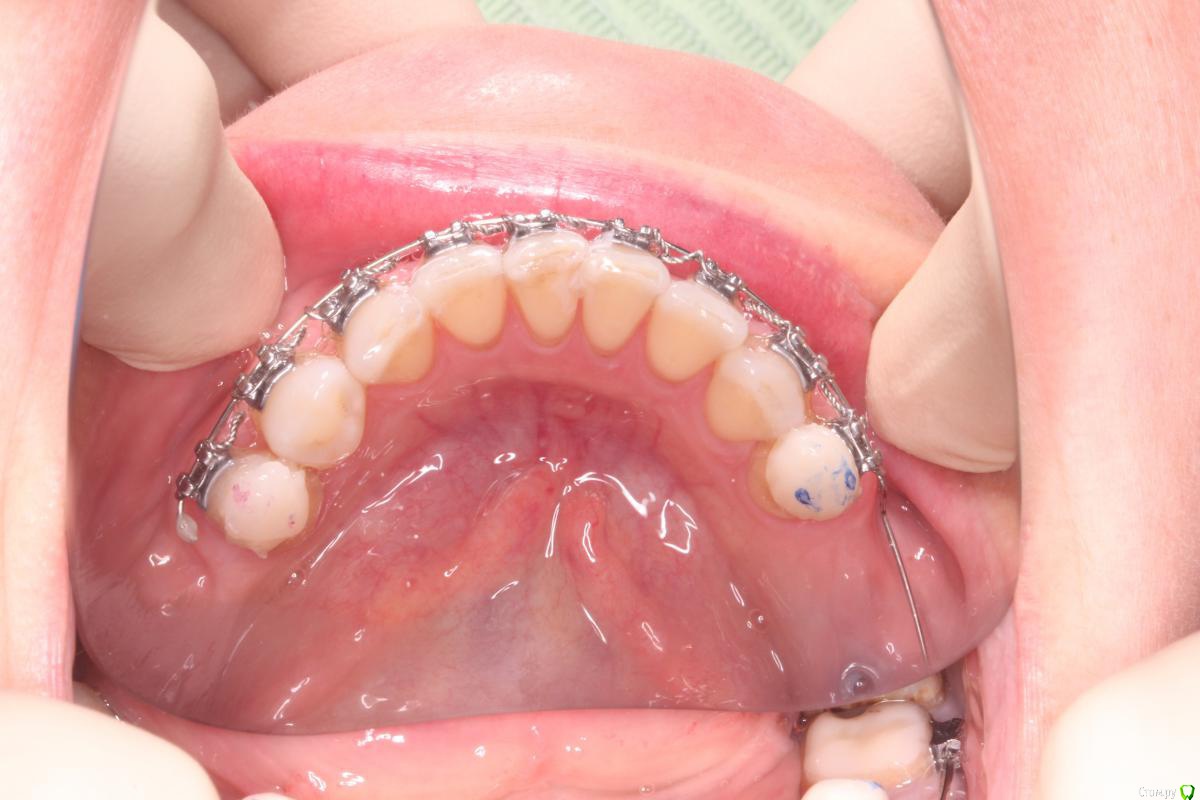

Monkey Опубликовано 2 сентября, 2015 Поделиться Опубликовано 2 сентября, 2015 Коллеги, посоветуйте, пожалуйста, что делать в таких ситуациях?Пациентке провожу нивелировку фронтального отдела нижней челюсти ( подготовка перед протезированием).Ни в какую не встает зуб 41.Изначально пружинами дистализировала по одному зубы: 45, затем 44,43,42, зуб не встал, видимо место было потеряно (давала восьмиобразную связку на перемещенные зубы). После этого сепарировала, и брекет несколько раз переклеивала ( в том числе с гиперкоррекцией), ни в какую. В чем тут дело? что я делаю не так? может быть недостаточно плотно лигирую?и как решить проблему? Ссылка на комментарий

Maverick Опубликовано 2 сентября, 2015 Поделиться Опубликовано 2 сентября, 2015 Причины : недостаток места, у вас весь фронт стоит зажато, будет место встанет все,далее: дуга не заполняет полнстью паз брекета, лигатуры слишком толстые по сечению и не удается плотно прижать при лигировании, сама дуга по сечению должна быть большого диаметра, чтобы заполнять паз брекета полнстью, сам брекет может быть наклеен не по оси, может быть под брекетом материал от фиксации, может быть виноват сам паз брекета, какой - то внутренний дефект. Попробуйте сделать изгиб и плотно залигировть , причем изгибы нужны будут на всем фронте и еще захватить клык. Потому что зубной ряд неровный. Дугу лучше использовать тма она мягкая, либо сталь если под рукой нет тма. Сечение 17х25 для тма, и 16х22 для стальной. 2 Ссылка на комментарий

Yana guapa Опубликовано 3 сентября, 2015 Поделиться Опубликовано 3 сентября, 2015 судя по фасеткам стираемости лигирование и переклейка здесь не помогут. Нижний зубной ряд нуждается в расширении. Но это невозможно при таком оверджет. Ну только если жесткий стрипинг. 1 Ссылка на комментарий

Yana guapa Опубликовано 3 сентября, 2015 Поделиться Опубликовано 3 сентября, 2015 думаю если убрать ок.накладки и проверить контакты - вся передняя поверхность нижних резцов окрасится. такие контакты плотные не дают стать ровно зубам. Надо расширять верх (ну или хотя бы изменить инклинацию верхних резцов) 2 Ссылка на комментарий

Monkey Опубликовано 3 сентября, 2015 Автор Поделиться Опубликовано 3 сентября, 2015 (изменено) судя по фасеткам стираемости лигирование и переклейка здесь не помогут. Нижний зубной ряд нуждается в расширении. Но это невозможно при таком оверджет. Ну только если жесткий стрипинг. Да, по перекрытию я смотрела, пространство (небольшое) есть. Я думаю, я еще сама связками (8-ками) заузила.Сейчас все зубы залигировала по одному и, действительно, попробую прямоугольную дугу- торк пойдет (брекеты на резцах 0*) может быть за счет этого расправятся...ну и плюс посепарирую еще.Спасибо за советы! Изменено 3 сентября, 2015 пользователем Monkey Ссылка на комментарий

Yana guapa Опубликовано 3 сентября, 2015 Поделиться Опубликовано 3 сентября, 2015 Да, по перекрытию я смотрела, пространство (небольшое) есть. Я думаю, я еще сама связками (8-ками) заузила. Про ВЧ речь идет?Были брекеты вверху? Сейчас все зубы залигировала по одному и, действительно, попробую прямоугольную дугу- торк пойдет (брекеты на резцах 0*) может быть за счет этого расправятся.... не думаю, что это поможет. при отсутвие должного оверджета не получится протрузии, а значит и разворачиваться некуда будет. и прямоугольная дуга не поможет при таком дефиците места. процесс пойдет только тогда, когда появится место. это либо 1. создание оверджета (за счет ВЧ), или 2. сепарация НЧ 3. как вариант дистализация премоляров (если окклюзионные контакты позволяют (как сейчас по прикусу в боковых отделах? есть фото?) ) Ссылка на комментарий